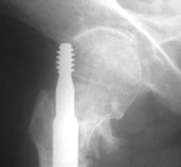

Seitlich wurde der Nagel fehlpositioniert, was

beim Belasten zum Auswandern führte. Mit dem Zielgerät

nach Asche wäre dies nicht passiert.